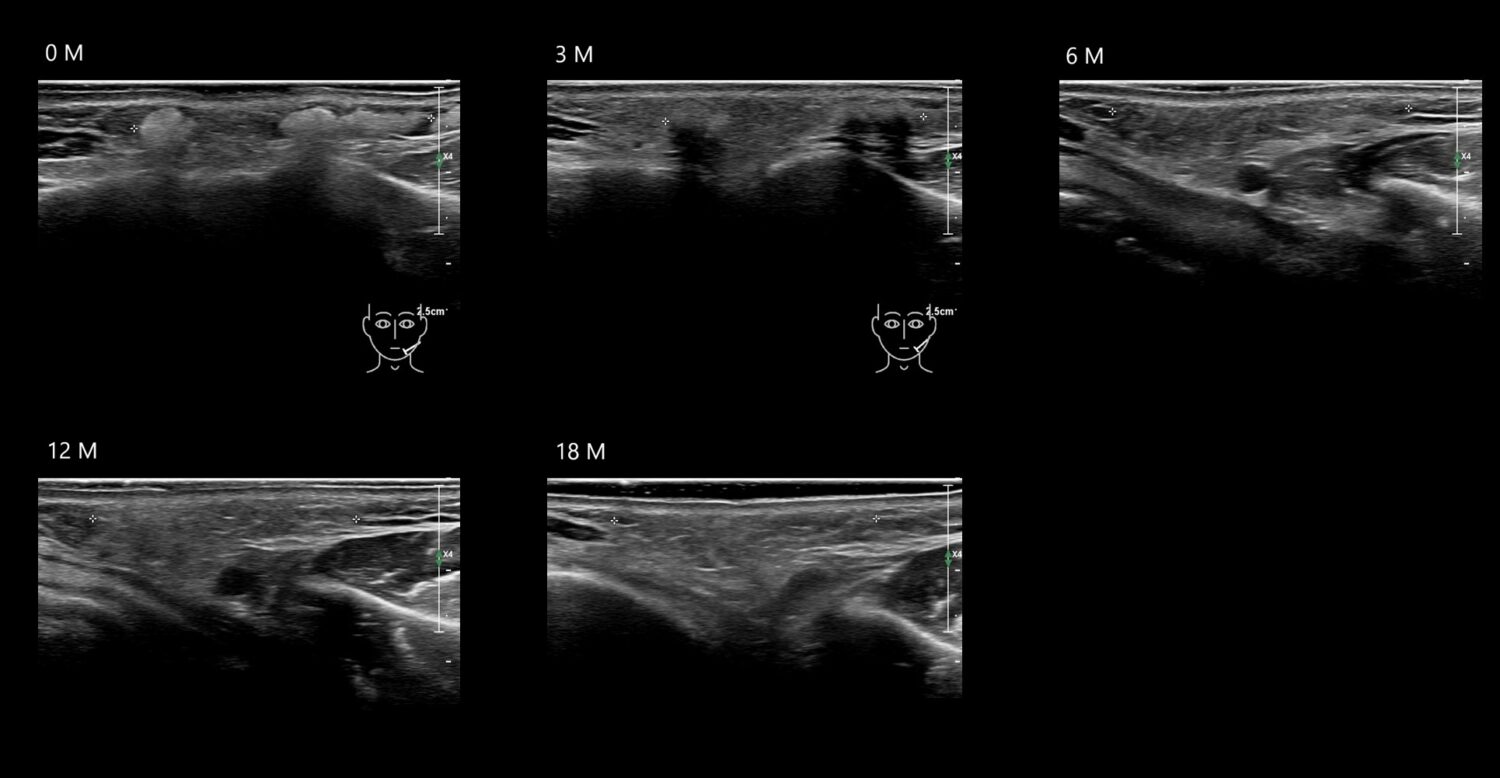

Fillers

Draw in the second image below where the fillers are located. To check if your answer is correct, swipe the first image to the right.